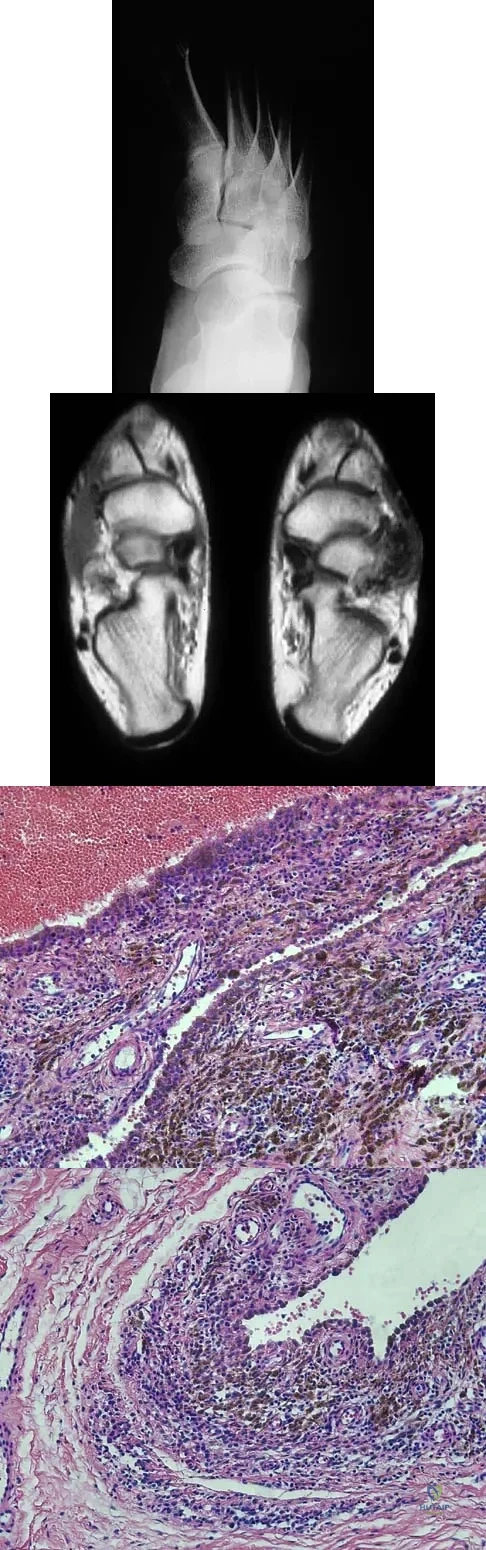

A 16-year-old girl has a painful foot mass. A radiograph, MRI scan, and biopsy specimens are shown in Figures 35a through 35d. What is the most likely diagnosis?

Explanation